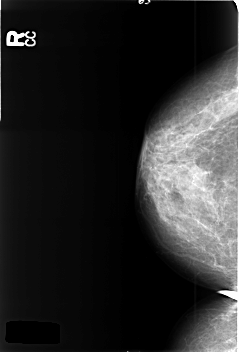

B_3374_1.RIGHT_CC

RIGHT_CC LINES 4568 PIXELS_PER_LINE 3096 BITS_PER_PIXEL 12 RESOLUTION 50 NON_OVERLAY